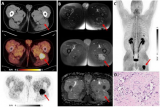

研究:通过Ga-68 FAPI-PET成像可识别罕见肿瘤

根据1月26日发表在《核医学杂志》上的一个病例,德国医生报告说,他们使用成纤维激活蛋白分子影像(68Ga-FAPI PET/CT),在一名新冠肺炎(COVID-19)患者的大腿上发现了一种罕见的腱鞘巨细胞瘤(TGCT)。